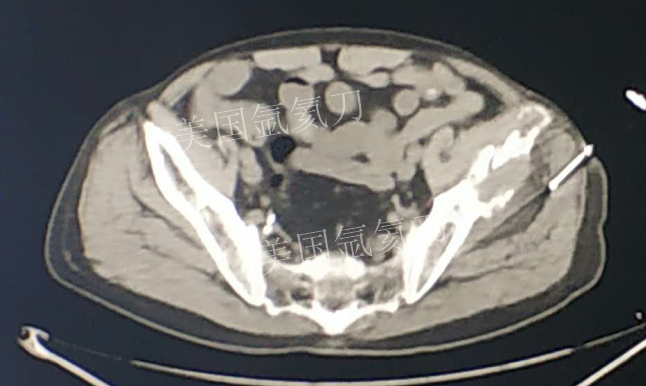

73岁臀部氩氦刀冷冻消融

发布人:美国氩氦刀技术官方网站    发布时间:2019/2/21 13:51:52